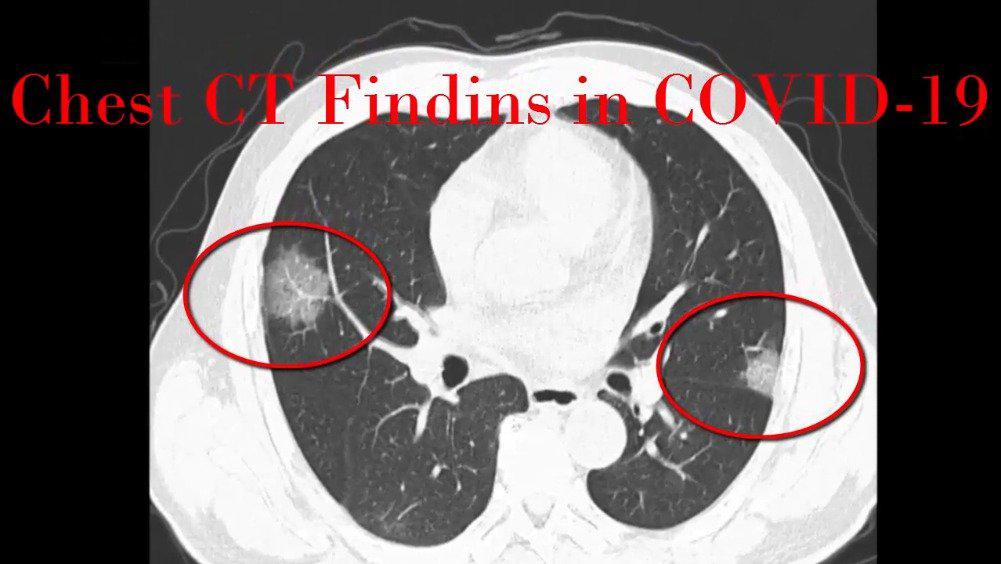

新冠肺炎ct表现

新冠病毒性肺炎典型ct表现,两肺多发磨玻璃密度影以近胸膜下为著